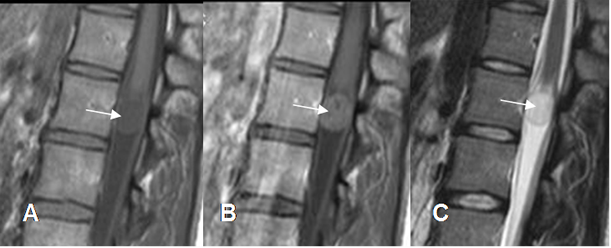

A: RM sagital en T1 simple, B: RM sagital en T1 con contraste y C: RM sagital en T2. Lesión expansiva en el cono medular, hipointensa en T1, hiperintensa en T2 y que realza con el contraste, sin porción quística, por astrocitoma.

Fig 237 A. Astrocitoma.